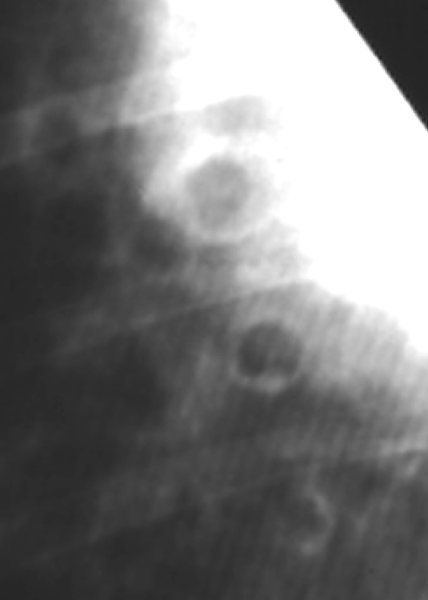

Q

Lung Pattern?

A